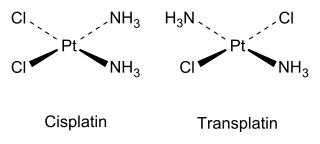

Cis and trans isomers also occur in inorganic coordination compounds, such as square planar complexes and octahedral complexes.

As an inorganic example, cisplatin (see structure above) is an important drug used in cancer chemotherapy, whereas the trans isomer (transplatin) has no useful pharmacological activity.